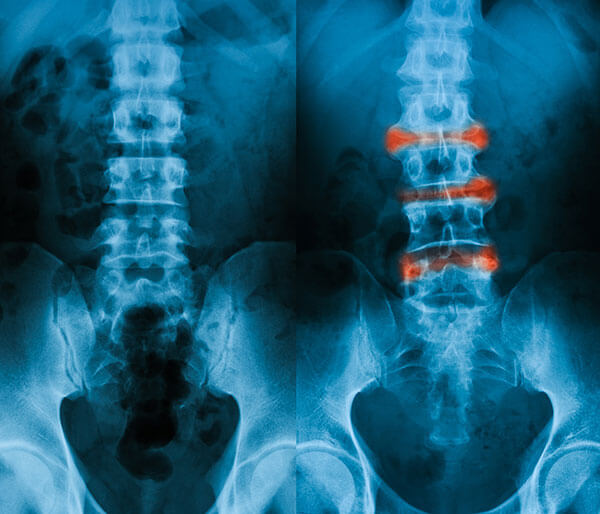

Am acesta boala de 12 ani si pana in momentul de fata nu am gasit nici un tratament care sa ma ajute am deja 2 operatii de protezare de sold si la stingul si la dreptul coloana este rigida mainile nu le pot ridica mai mult de nivelul umerilor gitul este prins in proportie de 95 genunchii si gleznele sunt prinse si ele nu ma pot apleca mai mult de. Spondilita anchilopoietica este o boala autoimuna de aceea raspunde foarte bine la tratamentul cu noni lichid care este un imunomodulator si un imunostimulator foarte bun. Spondilita anchilopoetica din comunitate. Constantin milică stil de viaţă spondilita anchilozantă este o leziune inflamatorie de natură reumatismală sau infecţioasă care afectează articulaţiile coloanei vertebrale cu evoluţie progresivă de cronicizare către anchiloză printr un proces de osificare făcând imposibilă mişcarea coloanei a umerilor şi.

Spondilita anchilopoietica sau anchilozanta tratament naturist complet. Spodilita anchilozanta inflamatie reumatismala a articulatiilor coloanei vertebrale cu evolutie progresiva spre anchiloza 0741 018 612 comenzi tratamentnaturist ro. Spondilita anchilozanta afecteaza mai ales barbatii cu varste cuprinse intre 20 si 40 de ani.